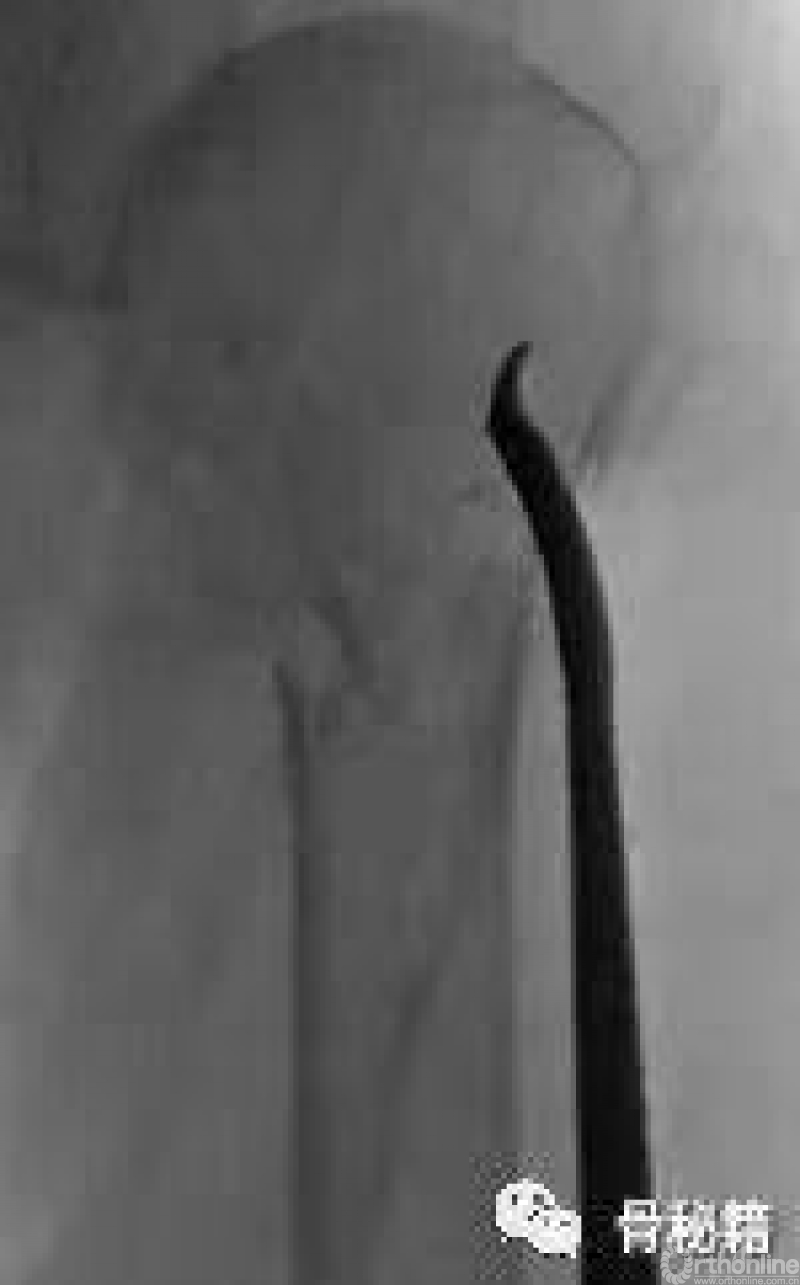

复位的关键就是将低头的肱骨头敲拨起来,外翻到合适的位置

可以应用摇杆技术等进行肱骨近端的复位,同时需要注意避让进针点的位置

也可以应用鞋拔子来进行翘拨复位,但是需要注意的问题是

外侧骨块必须是完整的,内侧一定要足够深入到头下的位置在骨量较好的地方进行翘拨